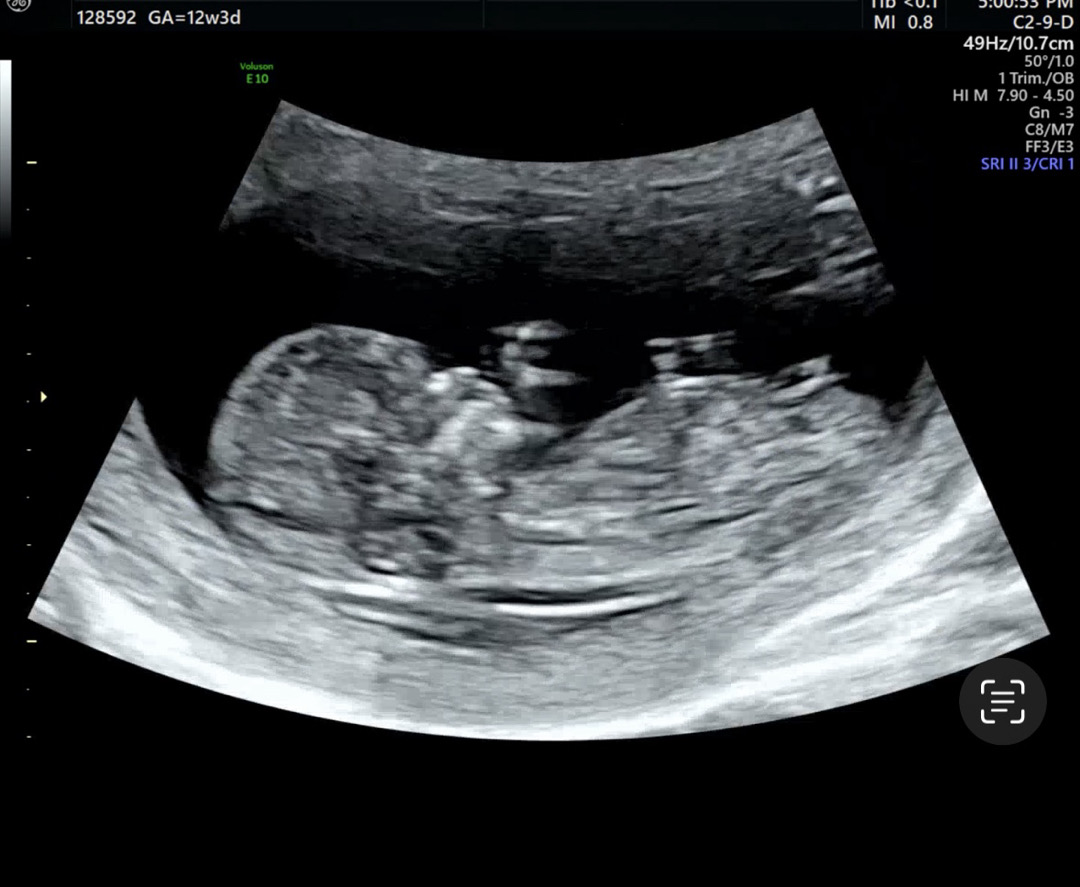

각도법. 12주 3일차 확인한번 부탁드립니당❣️

호옥시 각도법 잘 보시는분 계실까요? 넘 궁금해서 한번 올려봅니다!!! 😭